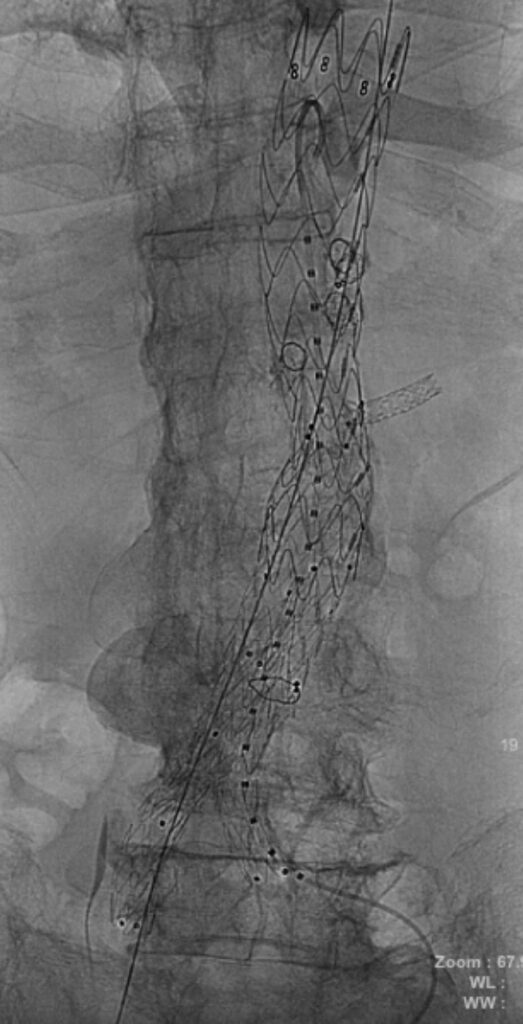

การผ่าตัดดังกล่าวใช้เทคนิค PMEG EVAR (Physician-Modified Endograft Endovascular Aneurysm Repair) ซึ่งเป็นนวัตกรรมขั้นสูงในการรักษาโรคหลอดเลือด โดยเป็นครั้งแรกที่โรงพยาบาลหาดใหญ่สามารถดำเนินการได้สำเร็จ ถือเป็นก้าวสำคัญในการยกระดับศักยภาพการรักษาโรคหลอดเลือดของโรงพยาบาลหาดใหญ่และพื้นที่ภาคใต้